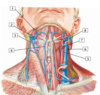

A

16

2

2 - retromandibular vein

Q

A

18

4

4 - anterior jugular vein

Q

A

20

6

6 - internal jugular vein

#7

30

#8 - transverse cervical artery

#9

31

#1 - superficia temporal artery

#2

33

#3 - internal carotid artery

#4

35

#5 - common carotid artery

#6

37

#7 - ascending pharyngeal artery

#8

39

#9 - facial artery

#10

41